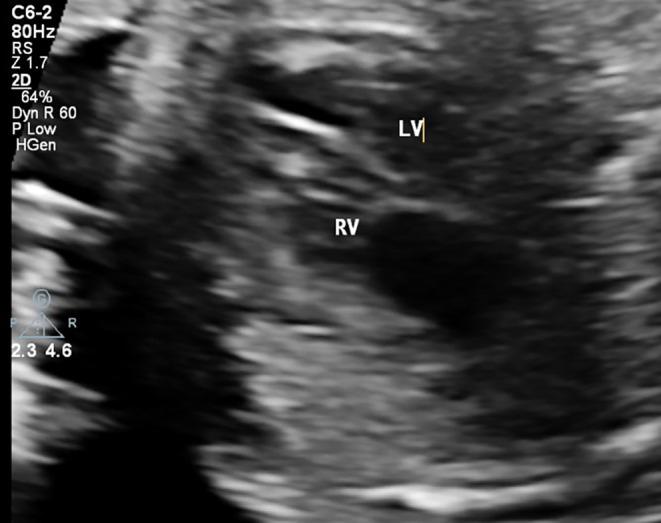

Premature Constriction of Fetal Ductus Arteriosus Caused by Sertraline in a Pregnant Woman: A Case Report.

Fetal ductus arteriosus was treated in a 39-year-old pregnant woman in the 33rd week After psychiatric consultation and discontinuation of sertraline which underscores the association of sertraline with premature ductus arteriosus constriction.

一名39岁的孕妇在孕33周时接受了胎儿动脉导管相关治疗。经过精神科会诊并停用舍曲林治疗,这突出了舍曲林与动脉导管过早收缩之间的关联。